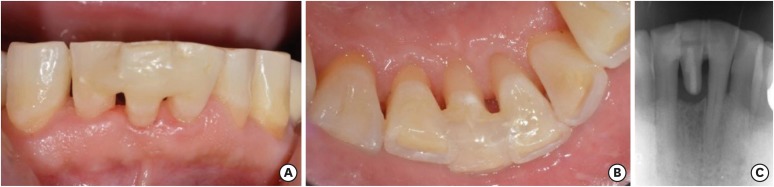

A 52-year-old man visited the Department of Conservative Dentistry because of mobility of the right mandibular central incisor (tooth #41) after it was smashed on a door 6 months previously. The tooth showed degree 3 mobility and slight tenderness on percussion. Clinical and radiographic examinations revealed that the tooth was root-fractured at the cervical third (Figure 1).

Figure 1

Preoperative view. (A) Intraoral photograph (labial view); (B) intraoral photograph (lingual view); (C) periapical view.